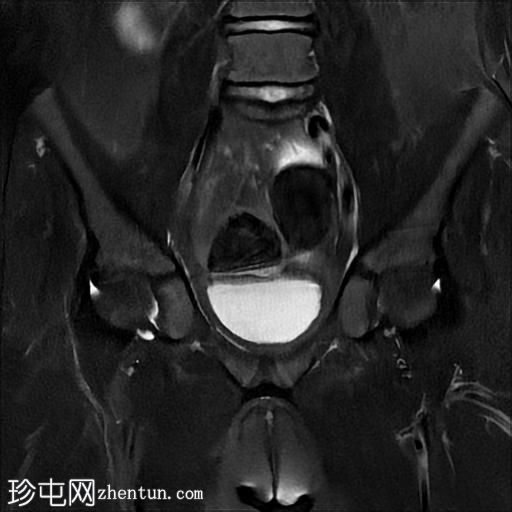

冠状面T2

脂肪饱和度

MRI序列显示:

女性外生殖器

子宫、宫颈及阴道上2/3缺失

左侧睾丸及腹股沟管内环

右侧睾丸位于腹腔内,靠近腰大肌

双侧卵巢未显影

MRI结果提示雄激素不敏感综合征 (AIS),患者基因构成为男性,但外生殖器为女性(46XY核型)。由于细胞对睾酮等雄激素产生抵抗,雄激素不敏感综合征常伴有双侧隐睾。

区分雄激素不敏感综合征与Mayer-Rokitansky-Küster-Hauser综合征(MRKH)至关重要。MRKH综合征具有女性核型,女性外生殖器和卵巢正常,但子宫缺失或发育不全。